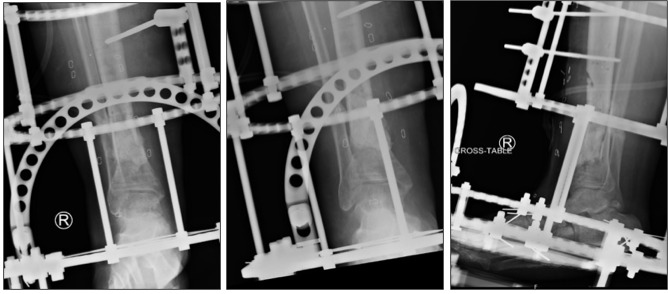

A 51-year-old morbidly obese, non-smoking male with a past medical history of type 2 diabetes, stage 3 chronic kidney disease, hypertension, and a previous gastric bypass surgery presents to the emergency department with a right ankle injury after a ground level fall while intoxicated. Radiographic imaging in the emergency department revealed a comminuted right distal tibial shaft fracture with extension into the tibial plafond, and an associated nondisplaced distal fibular fracture (Figure 1). At the time of orthopedic consult which was less than 24 hours after the initial injury, physical exam revealed the leg neurovascularly intact with no fracture blisters forming on the skin. At that time the soft-tissues were deemed amenable to immediate fixation and the patient was taken the same day for definitive ORIF using a dual locking plate construct (figure 2).

At this time, care was transferred to a fellowship-trained orthopedic traumatologist as there was concern for deep infection resulting in delayed and compromised fracture healing. Since the patient was still showing clinical signs of infection and no healing observed on films, it was elected to undergo a second irrigation and debridement with removal of hardware and placement of a skinny wire frame external fixator. An excisional debridement of all nonviable bone had been performed at this time. An antibiotic cement spacer mixed with 1.4g gentamicin and 1g vancomycin had been inserted into an extra-articular bone void measuring approximately 3x2x2 cm. While maintaining the midsubstance of the incision open, the edges of the previous incision were closed primarily and a wound vac was placed. Appropriate antibiotics were again determined from the intraoperative cultures, this time positive for C. striatum.

At the eighteen weeks, radiographic imaging continued to show signs of nonunion. There was discussion at this time that the delayed union was in part due to lack of structural support (Figure 3). The decision was made to undergo repeat I&D with removal of cement spacer and bone grafting in an attempt to stimulate union, followed by definitive coverage of the wound with a split thickness skin graft (Figure 4).